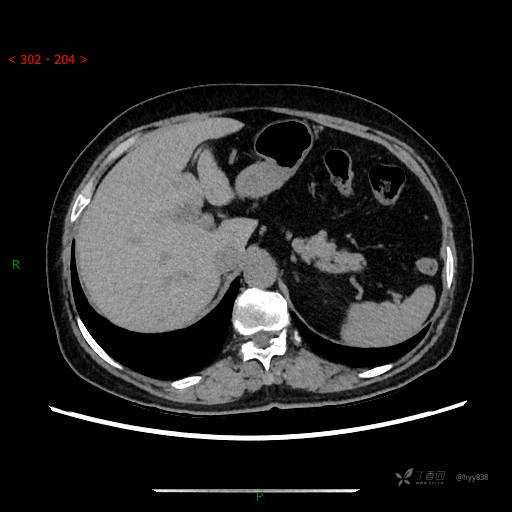

静脉期